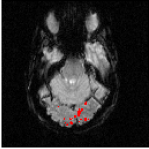

The Experience Based Cognition competition (EBC) (University of Pittsburgh, 2007) offers an opportunity to study complex responses to natural environments. The EBC datasets comprise three 20-minute runs (704 TRs in each run) of subjects interacting in an urban virtual reality environment. Subjects were audibly instructed to complete three search tasks in the environment: looking for weapons (but not tools) taking pictures of people with piercing (but not others), or picking up fruits (but not vegetables). The data was collected with a 3T EPI scanner (TR = s, xy dimension: , voxel size = mm, 34 slices with a thickness of mm). We analyze the second runs of subjects 14 and 13. For each subject, the matrix is composed of intra-cranial voxels at TRs. We first remove the non regionally specific variance captured by the first eigenmodes of a singular value decomposition of the dataset. We then compute using and . After embedding the dataset into four dimensions, we cluster the voxels. Figs. 18 and 20 display the datasets after embedding. Because we cannot display four dimensions, we show the projections of the dataset on three consecutive coordinates. All the coordinates contribute to the spread the dataset along elongated arms, which facilitates the clustering. Voxels that do not correspond to the background activity (the maroon cluster in Figs. 18 and 20) are superimposed on anatomically registered structural images and colored according to their cluster label (see Figs. 19 and 21). For both subjects, the clusters are connected regions (see Figs. 19 and 21), compactly organized around functional areas related to the processing of visual, and auditory stimuli (music, cellphone ringing, dog roaring) in the virtual environment. It is important to emphasize that our method never enforces any form of spatial proximity, and is purely based on functional connectivity.

For subject 14 (Fig. 19), the orange cluster corresponds to activation in the calcarine cortex associated with V1/V2 representations of the lower visual fields, while the light blue cluster corresponds to representations of the upper visual fields. Activation in lateral areas (visual motion areas, MT/V5) is also present, as well as activity in the posterior convexial cortex (area VP). The activation is predominantly in the right hemisphere. Interestingly, the two clusters located in the visual cortex (light blue and orange) have very similar and coordinates (see Fig. 18-left). The cyan cluster corresponds to activation in the right frontal gyrus (Broca area) associated with language comprehension. The yellow clusters are located in the right and left superior temporal gyri and medial temporal gyri (Wernicke area). These regions correlate with activation

in the auditory cortex and language areas. Finally, the dark blue cluster corresponds to activation in the prefrontal cortex. A very similar pattern of activity (Fig. 21) was obtained for subject 13. The blue and orange clusters, located in the calcarine cortex, correspond to V1 and V2 areas. Again, these two clusters, both located in the visual cortex, have similar and coordinates. The green cluster is located in the medial temporal gyrus (Wernicke area) and is associated with language processing.